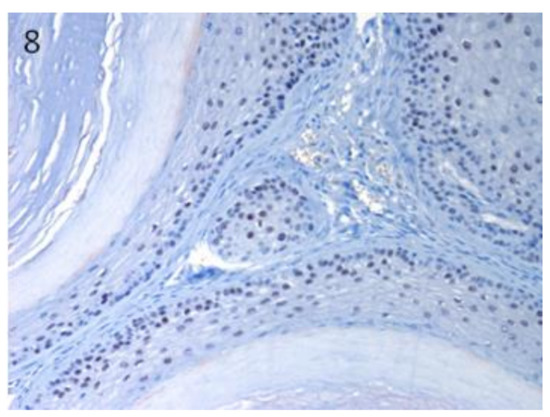

3.1. Stem Cell Marker Analyses in Healthy Skin. Sox9 and Lgr5 Protein Expression was Confirmed in Specific Regions of Canine Hair Follicle